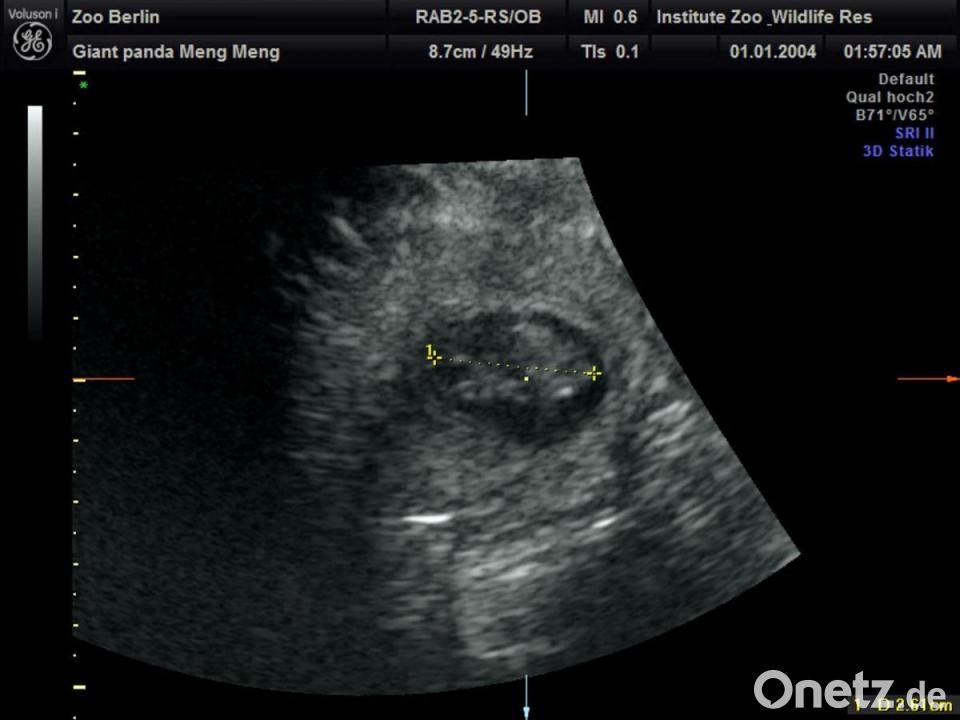

Im Berliner Zoo wird wieder Panda-Nachwuchs erwartet. „Die Babys sind etwa 2,5 Zentimeter groß und müssen jetzt bis zur Geburt noch ordentlich wachsen“, sagte Thomas Hildebrandt, Leiter der Abteilung für Reproduktionsmanagement am Leibniz-Institut für Zoo- und Wildtierforschung laut Pressemitteilung. Im Panda Garden sei am Sonntag ein kleiner Jubel ausgebrochen, teilte der Zoo mit. Die Panda-Dame hatte sich zuletzt nicht besonders kooperativ gezeigt. „Trotz sichtlichen Bauchkneifens“ habe Meng Meng sich aber überzeugen lassen, „in den aufrechten Stand zu kommen und das kühle Ultraschall-Gel sowie die Untersuchung mit der Ultraschall-Sonde zu akzeptieren“, sagte der Veterinärmediziner, der als internationaler Experte bei der Reproduktion von Großen Pandas gilt. „Eine Untersuchung im Stehen hat schließlich die freudige Nachricht gebracht, dass Meng Meng mit zwei Jungtieren trächtig ist.“

Die Freude im Team sei riesig gewesen, weil es schon einige erfolglose Ultraschallversuche gegeben habe, sagte Zootierärztin Franziska Sutter, die ebenfalls an der Untersuchung beteiligt war. „Bei aller Begeisterung müssen wir uns darüber im Klaren sein, dass das ein sehr frühes Stadium der Trächtigkeit ist und eine sogenannte Resorption – also ein Absterben - des Embryos zu diesem Zeitpunkt noch möglich ist“, sagte Sutter. Die Tragzeit beträgt bei Großen Pandas in der Regel drei bis sechs Monate.